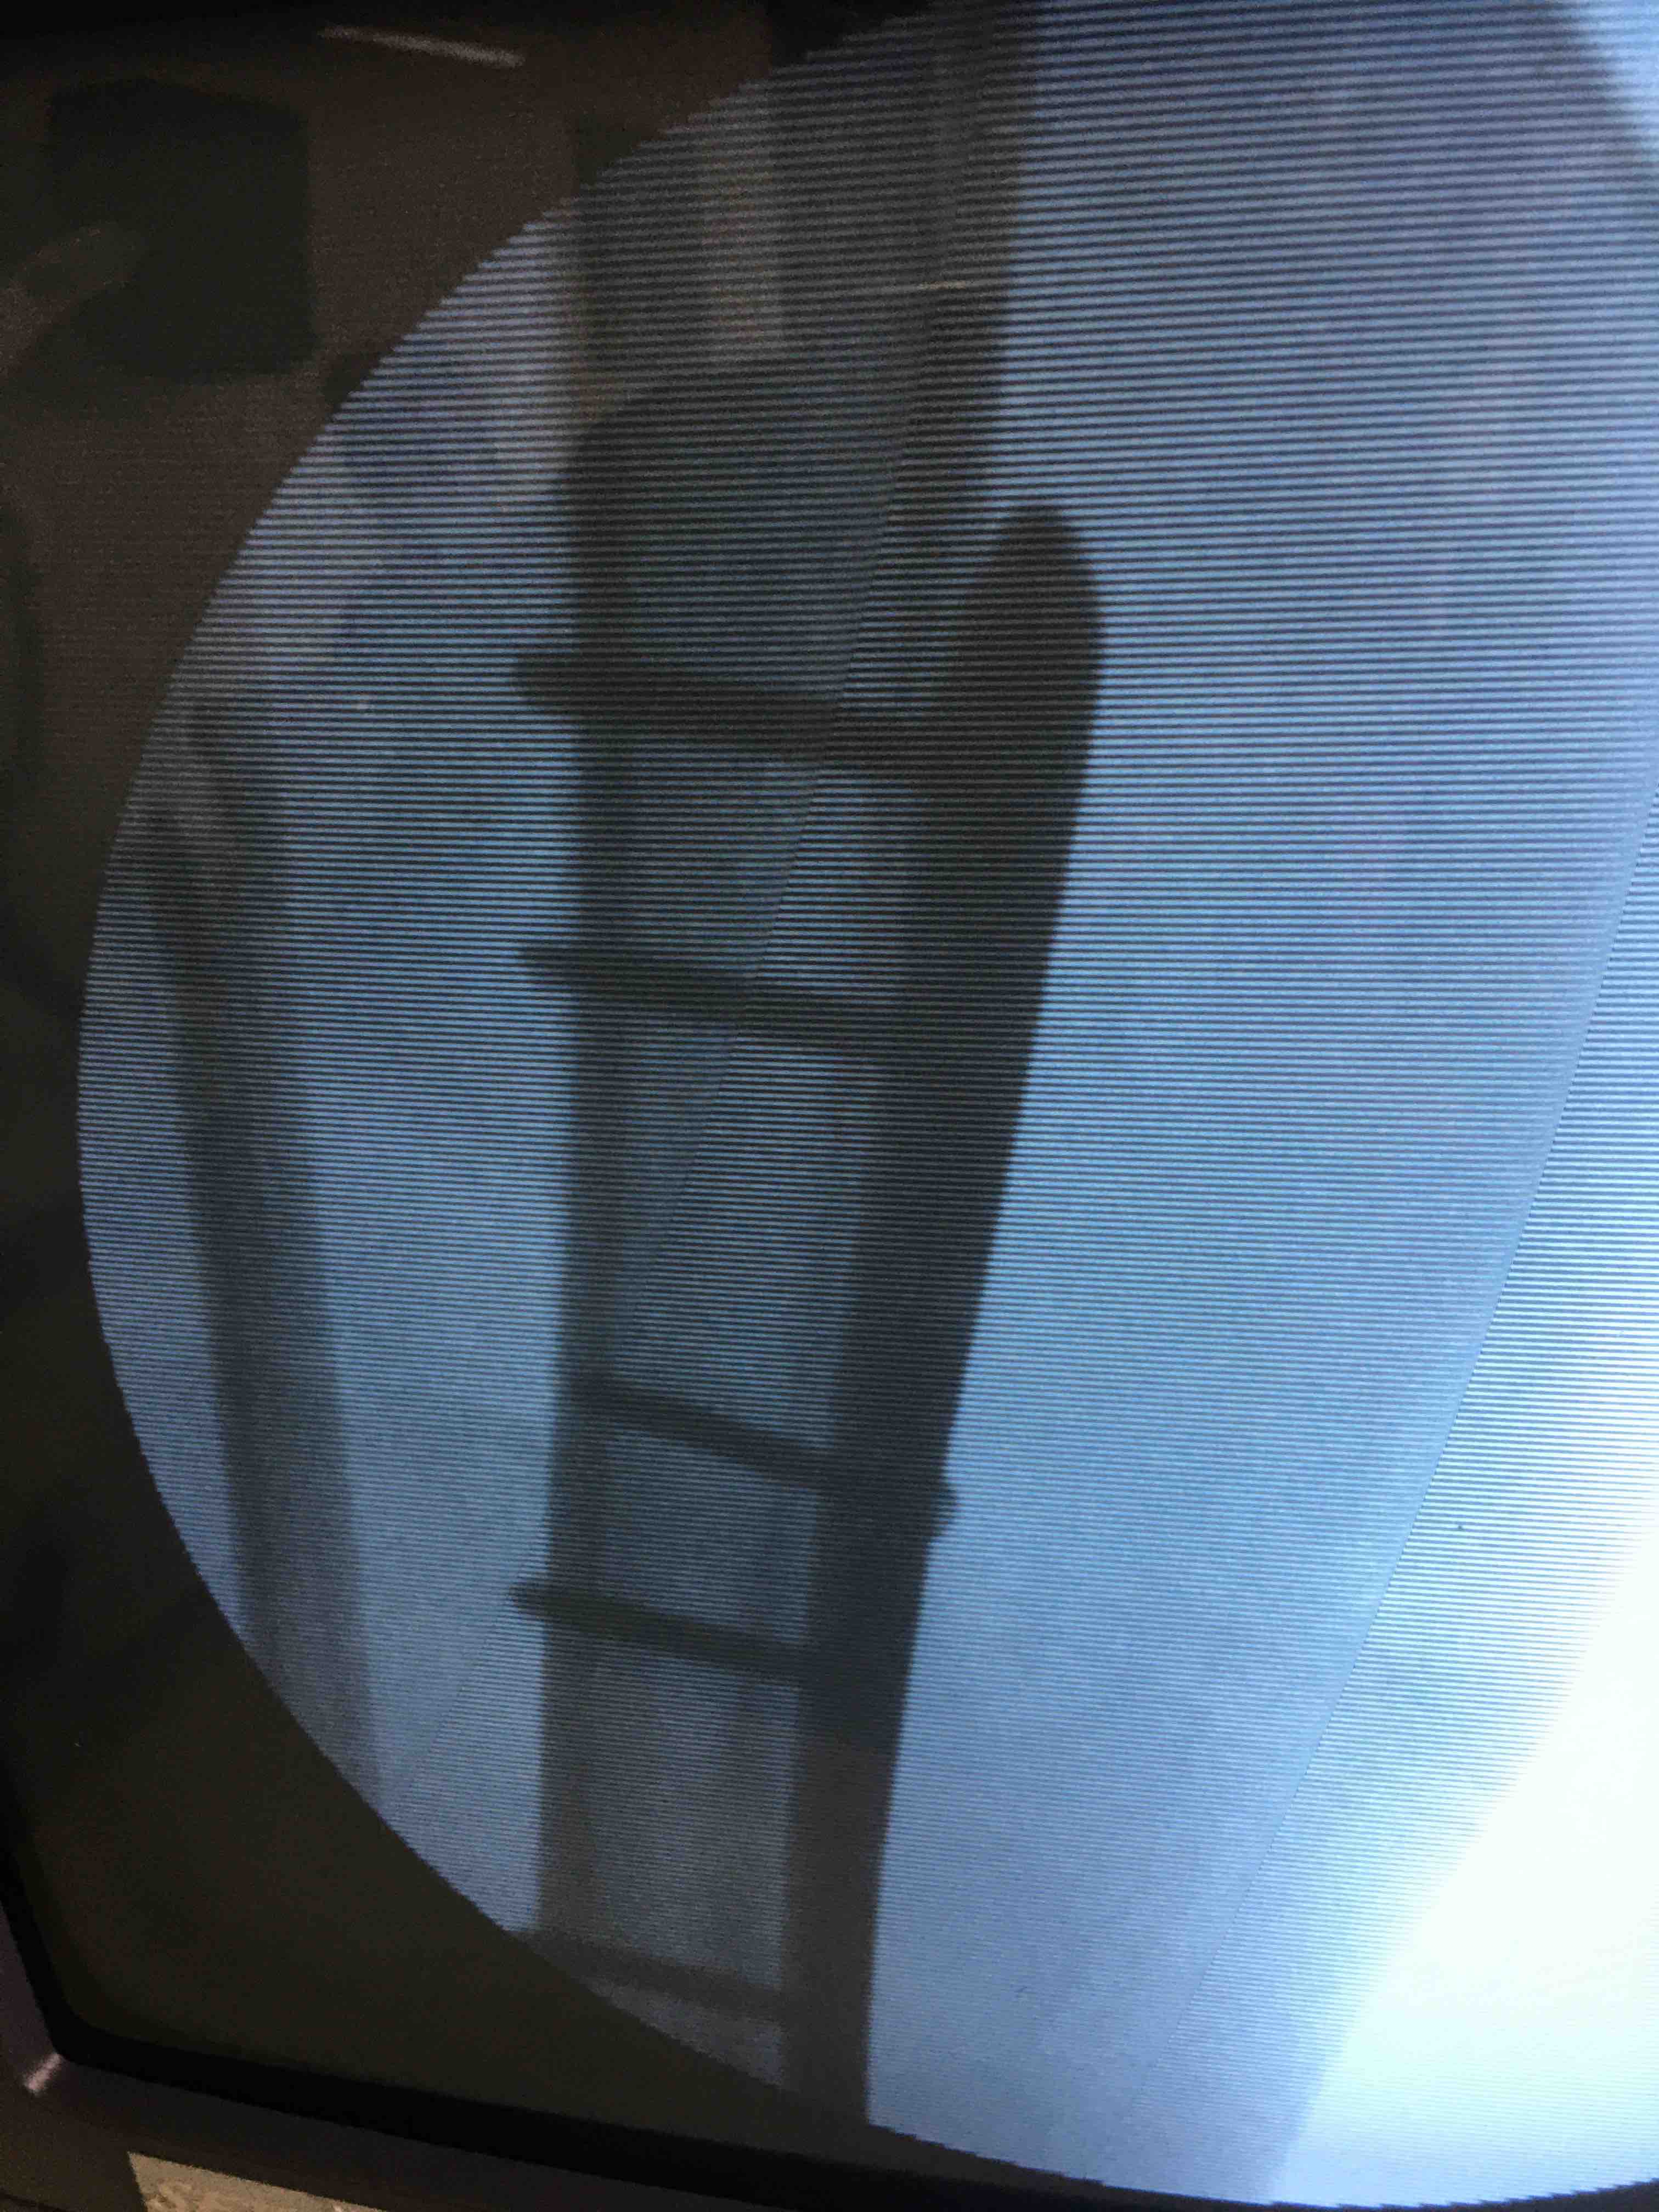

胫腓骨下段骨折(微创固定)

摔伤后右小腿肿痛,活动受限1小时入院。既往身体健康,无特殊不良嗜好。

生命体征平稳,心肺复未见明显异常。右小腿肿胀,局部皮色皮温正常,压痛及叩痛阳性,可及骨擦音,活动受限,末梢血运感觉正常。

在腰麻下行切复内固定术,术后抗炎,消肿对症治疗。